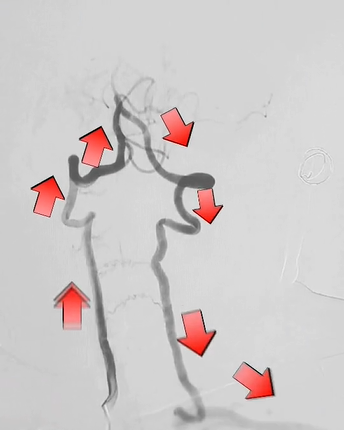

最终造影,验证通畅:

wuwei